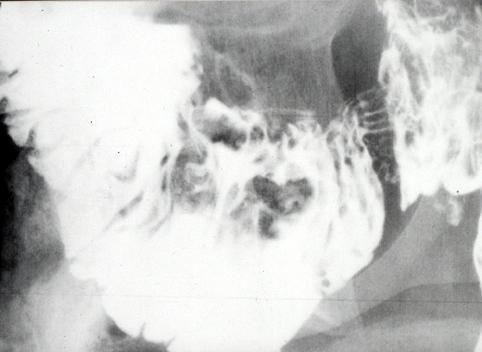

Linfoma Maligno constituído por múltiples lesiones elevadas esencialmente en el Intestino Delgado----Caso de los años 1970

[Image-ID:5502]

Tumor Maligno del Sistema Linfático/Linfoma Maligno

duodeno/horizontal

método de exámen

Rayos X

diámetro mayor del tumor

25 - 29

múltiples tumores(en un mismo órgano)

presente(simultáneo)

múltiples tumores(en varios órganos)